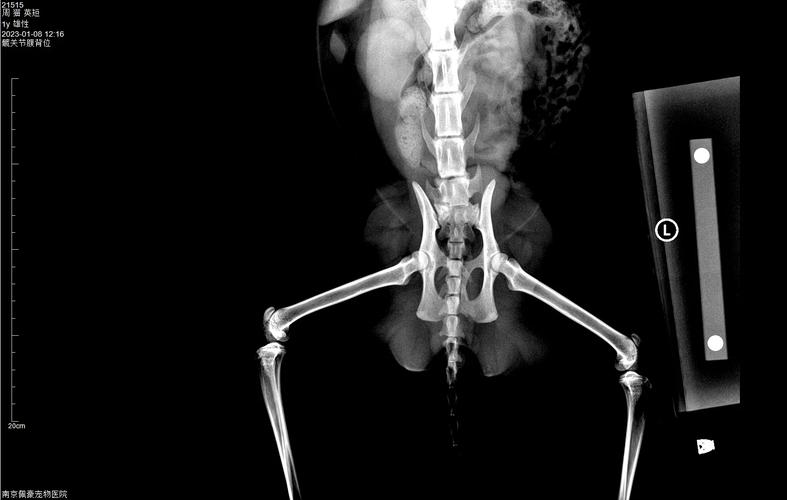

髋关节发育不良:髋关节发育不良是一种遗传性疾病,表现为髋关节发育不全或结构异常。症状包括行走困难、后肢无力和关节疼痛。诊断通常通过X光检查进行,治疗可能包括手术矫正或限制活动以减轻症状。脊柱侧弯:脊柱侧弯是指猫咪脊柱向一侧弯曲,可能由遗传、肌肉不平衡或神经肌肉疾病引起。

导致猫咪腿部疼痛的原因有很多,关节炎、关节损伤、软组织拉伤、骨折、外伤等都可能导致腿疼,并且后肢不能完全着地行走。如果是骨头的问题,需要带猫咪去宠物医院拍X光片检查才能确诊和治疗。